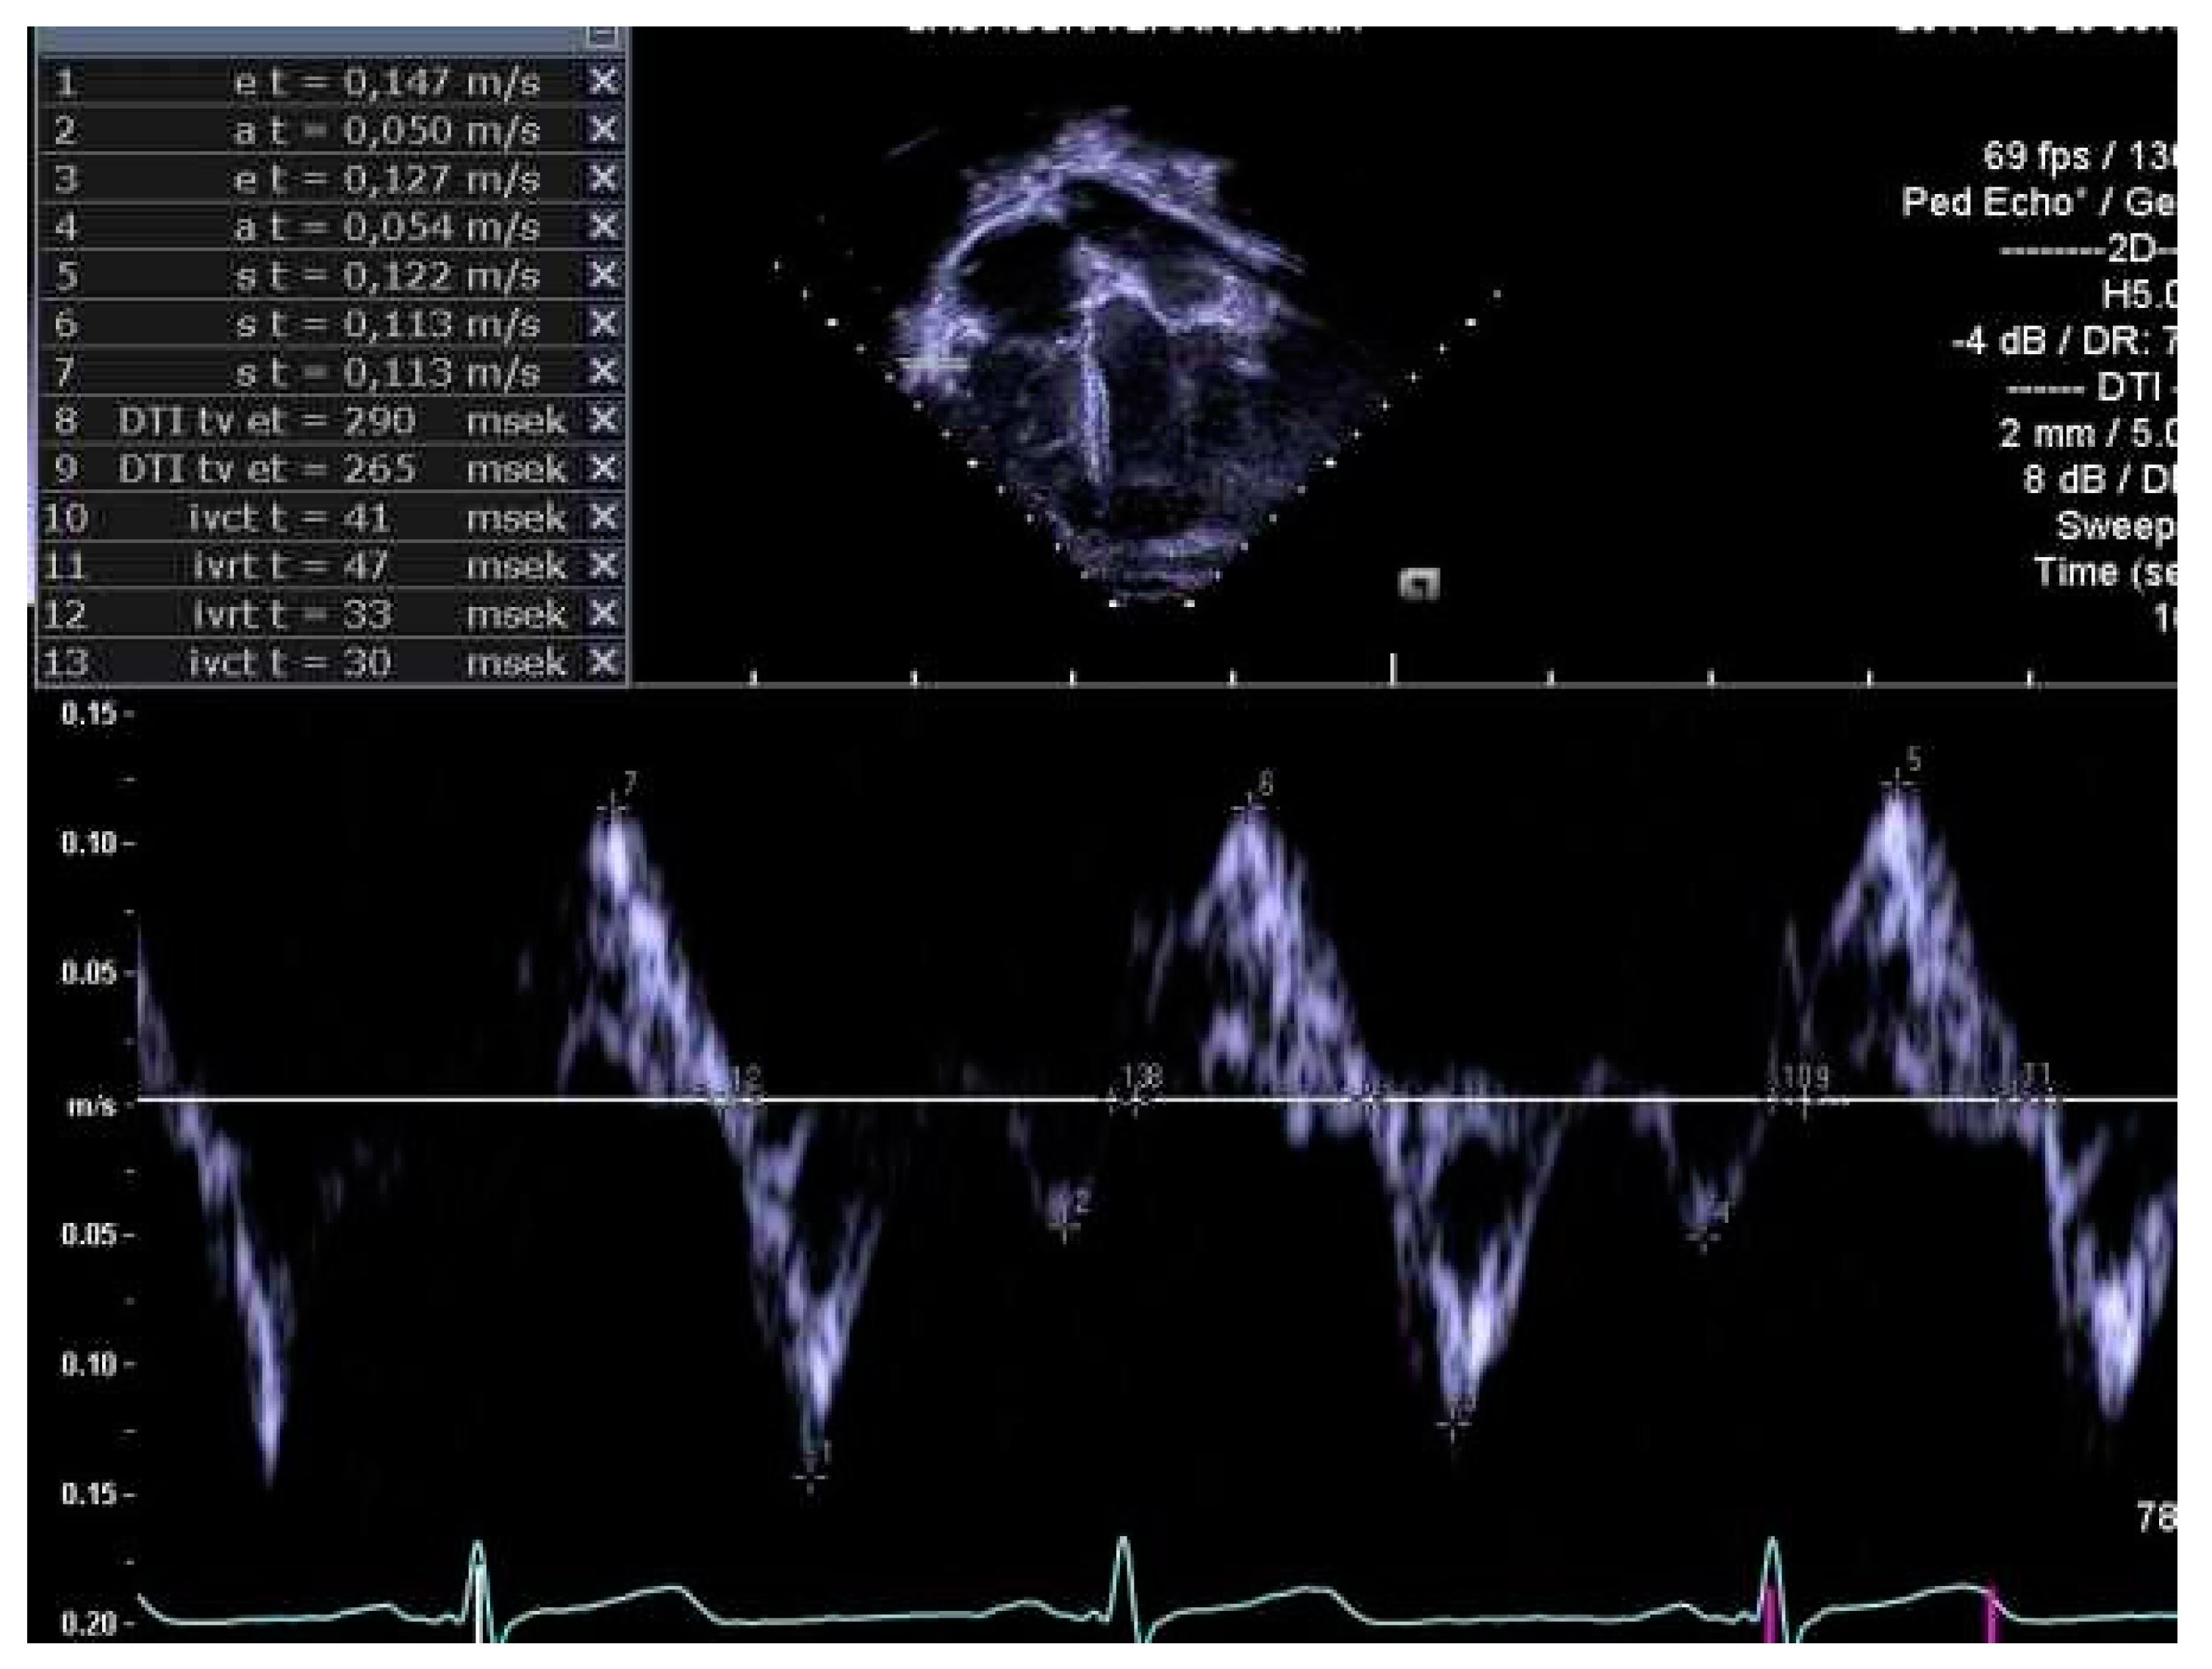

2.4. Determination of Right Heart Outcome Variables

3.5. Right Heart Systolic and Diastolic Functions

3.6. Perinatal Risk Factors and Right Heart Structure and Function in Children Born Extremely Preterm